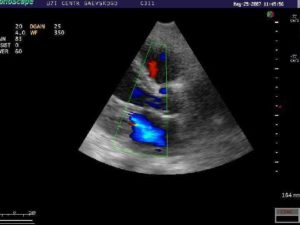

| Эхокардиография |

|

- Нарушение подтверждается на ЭхоКГ. Ультразвуковой метод выявляет увеличение камер сердца и неполное закрытие митрального отверстия.

На ЭхоКГ – утолщение створок клапана, кальциноз, расширение левого предсердия, регургитация митрального клапана III степени.